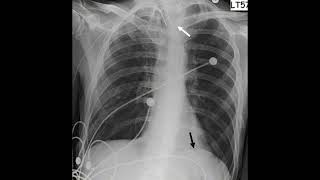

FRCR 2B RS Case 06